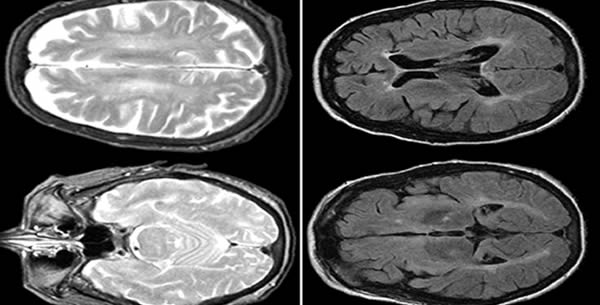

Neimann-Pick-ova bolest odnosi se na grupu nasljednih metaboličkih poremećaja poznatih kao leukodistrofije ili poremećaji razgradnje lipida. Kod takvih bolesti dolazi do nakupljanja štetnih količina masti u organima poput slezine, jetre, pluća, koštane srži i mozga.

Deficijentnost enzima sfingomijelinaze nasleđuje se autosomno recesivno i uzrok je deponovanja sfingomijelina i holesterola u lizozomima ćelija retikuloendotelnog sistema mozga.